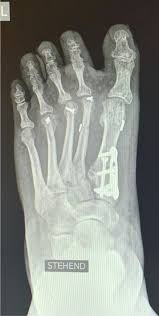

Komplikationen Der Tarsometatarsale I Arthrodese Modifizierte Lapidus Arthrodese Sciencedirect